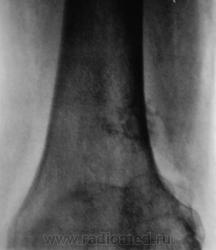

Пациентка направлена на рентгенографию коленного сустава с диагнозом "Деформирующий артроз".

Выраженный деформирующий артроз, множественные хонтроматозные тела в полости сустава.